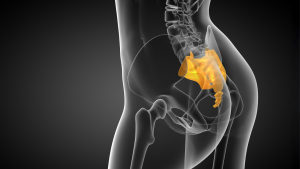

Leia maisDor e inchaço no cóccix: o que pode ser?

Desconfortos próximos ao cóccix podem gerar preocupação e...